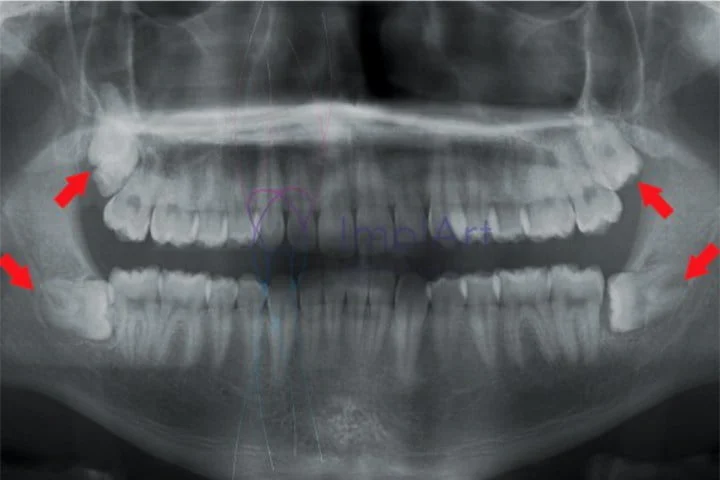

Aqui vamos explicar tudo sobre os sisos e te tranquilizar para que você possa realizar suas extrações sem maiores preocupações...